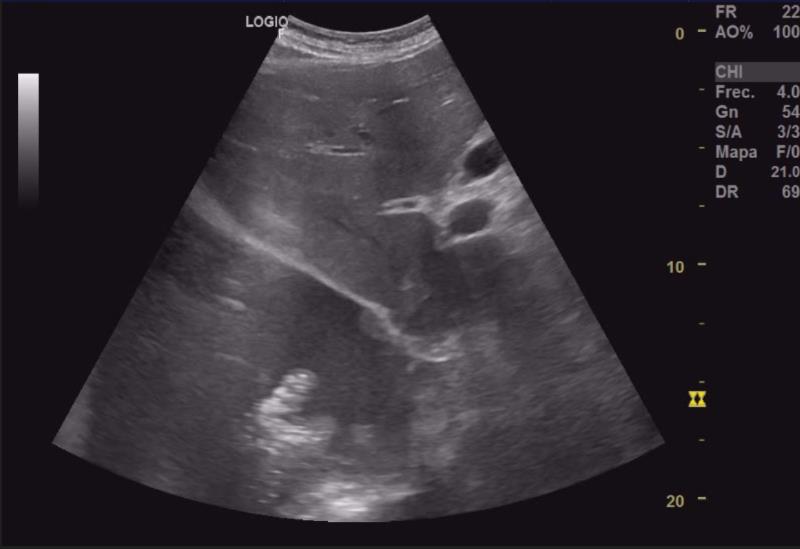

Importante colección anecoica supradiafragmática compatible con derrame pleural masivo (2/3 pulmón derecho), con flóculos ecogénicos (tongue-like sign) sugerentes de parénquima pulmonar atelectásico. Escasa colección anecoica pericárdica. Se identifica en riñón izquierdo una imagen heterogénea de bordes bien definidos en polo superior invadiendo pelvis, de unos 52x58x60 mm, con aumento de captación doppler.Pruebas complementarias